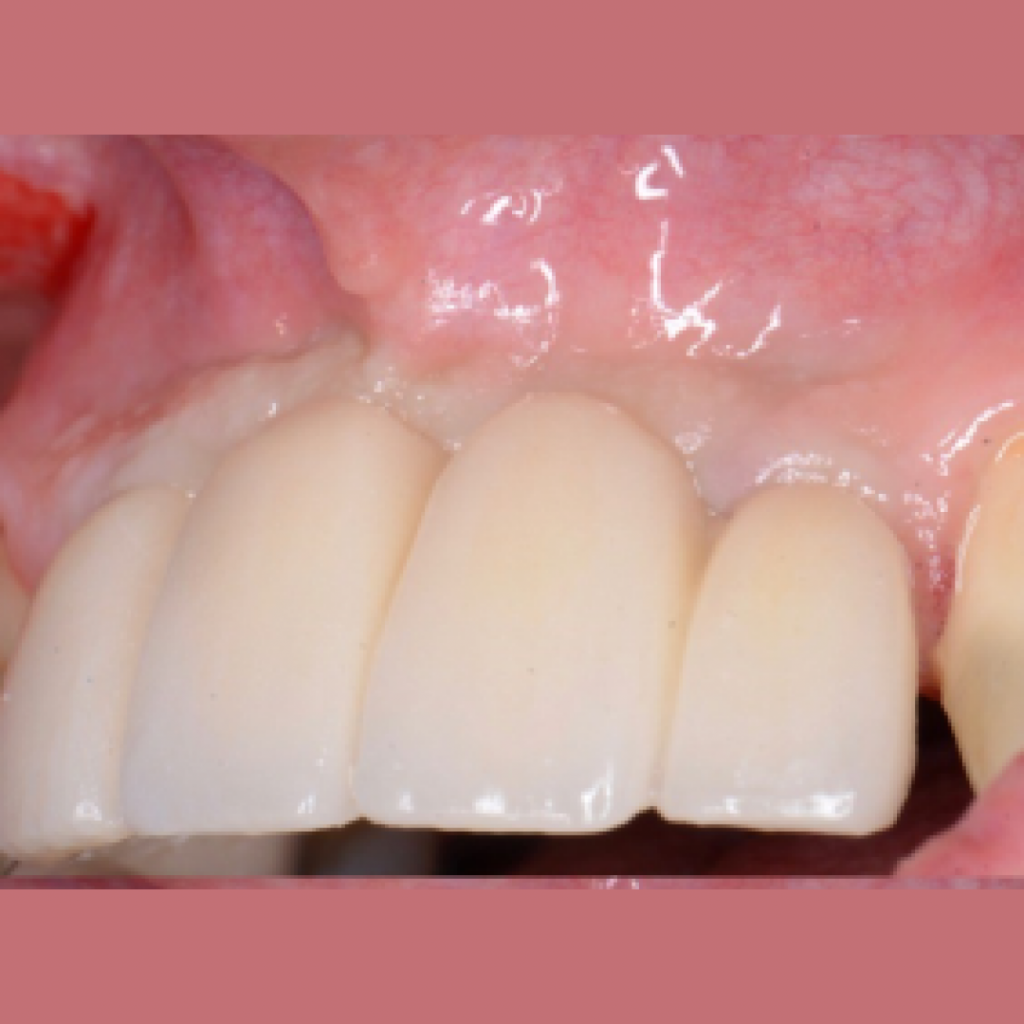

Имплантация AnyOne в узкий гребень. Восстановление зубов 11,12,21,22 на двух имплантатах.